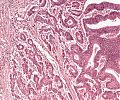

A82 Appendix-Karzinoid

Große, nestartige Verbände neuroendokriner Tumorzellen

A82 Appendix-Karzinoid

Tumorzellnester und diffuse Infiltration der neuroendokrinen Tumorzellen

Appendixkarzinoid

Erkennbar sind isomorphe Tumorzellnester

Appendixkarzinoid

Neuroendokriner Tumor mit nestartigen, trabekulären Formationen isomorpher Tumorzellen